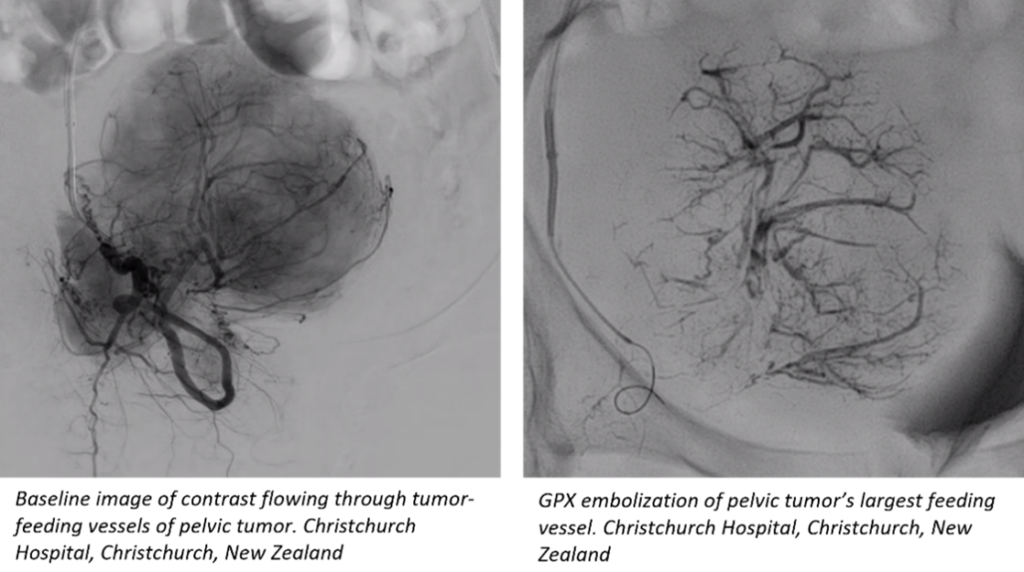

Fluidx Medical announces completion of trial enrollment for its novel embolic device, GPX. In this multi-center trial, GPX was used to treat a variety of primary and metastatic tumors, renal adenoma tumors, and a range of other arterial and venous applications.

GPX has shown promising results for tumor embolization and other uses where there is a desire for distal vessel bed penetration. Embolization is a procedure in which arterial or venous blood supply to an organ, malformation, aneurysm, bleed, tumor, and/or other abnormal area of issue is blocked. Interim results of the GPX study have been presented at recent annual congresses including Global Embolization Symposium & Technologies (GEST), Society of Interventional Radiology (SIR), and Leipzig Interventional Course (LINC).